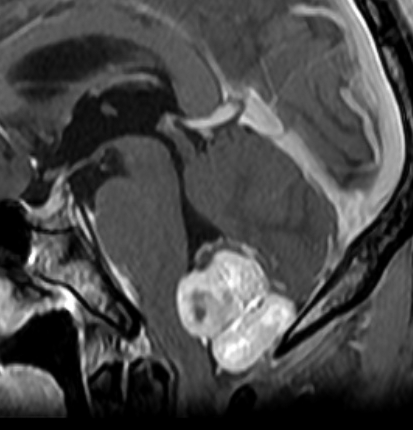

ものすごく難しい血管芽腫

これも血管芽腫です。おそらく小脳発生なのでしょうが,延髄の両側に強く癒着していて延髄の血管も腫瘍の中に入っていて,腫瘍血管には動脈瘤も合併していて破裂しました。この腫瘍を摘出するのは不可能にも思えましたが,無事にできました(下の写真)。患者さんも私もへとへとになりました。 でも,このような血管芽腫の手術はうまく行くとは限りません,手術不可能と考えた方がいいかもしれないと今でも思っています。手術すると決めればものすごく高いリスクを患者さんも外科医も背負うことになります。放射線治療をして治るサイズではないので他に治療法はありませんが (>_<) 大きな血管芽腫を手術する提案をされたら,少なくとも執刀医の経験数は尋ねましょう。